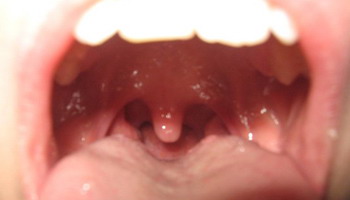

Bocca

- Focolai di Hamer: 1, 3 e 24 del Tronco Cerebrale.

- Funzione: è la apertura corporea attraverso la quale si introducono gli alimenti. È la prima parte dell'apparato digerente.

Sottomucosa, lingua, adenoide, parotide, regione sublinguale, sottomandibolare (salivare), faringe (gola)

- Senso della Attivazione (Conflitto): non poter afferrare la preda, l'obiettivo, il profitto, il boccone. Non poter possedere, conseguire qualcosa.

- Fase Attiva: ispessimento della mucosa, polipi nasali, adenocarcinomi, con crescita a cavolfiore, a qualità secretoria. Mucoviscidosi delle Ghiandole parotidi e sublinguali (salivazione).

- PclA: bocca secca, alitosi, ulcera aftosa (mughetto), afte buccali, funghi (micosi, candidiadi), micobatteri (TBC), caseificazione fetida.

- Crisi epilettoide: salivazione.

- PclB: salivazione, alitosi, mughetto, sanguinamento.

- Normotonia: resti cicatriziali.

Palato, tonsille, paratiroidi

- Senso della Attivazione (Conflitto): non poter ingoiare la preda, sebbene la si sia afferrata, non poter ingoiare un boccone che lo si è già addentato. Non poter ingoiare un boccone già praticamente avuto, doverci rinunciare.

- Fase Attiva: adenocarcinoma compatto che cresce a forma di cavolfiore a qualità secretoria o adenocarcinoma a crescita piatta a qualità assorbente della antica mucosa intestinale (sotto all'epitelio pavimentoso orale).

Iperplasia / ipertrofia delle tonsille.

Tonsille ingrossate quando si sono avute varie recidive (Pcls).

Iperparatiroidismo. - Fase Pcl: riduzione caseosa fetida e purulenta. riduzione ad opera di funghi (micosi) o micobatteri (TBC). Tumori incapsulati.